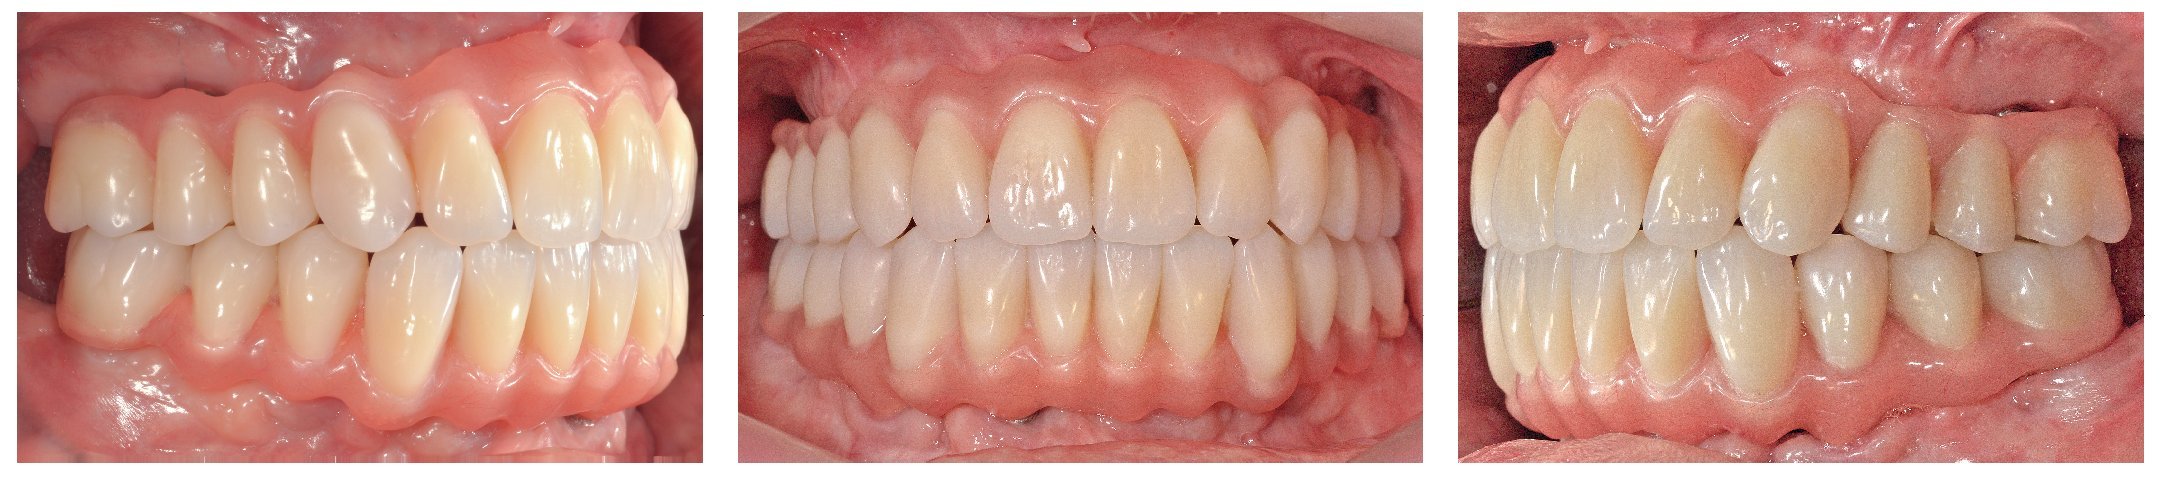

Pese a ello, es importante someter las estructuras a un control visual y mecánico, a fin de corregir eventuales discrepancias menores (figs. 99 a 102). A continuación se procede al montaje utilizando dientes protésicos prefabricados de composite (SR Phonares NHC, Ivoclar Vivadent, Ellwangen, Alemania), los cuales reproducen el tipo funcional correspondiente en virtud de sus propiedades morfológicas y estructurales y se integran armoniosamente en cuanto a su longitud dental (figs. 103 a 105). Durante la comprobación de las restauraciones protésicas, se evalúan clínica y radiológicamente ante todo la pasividad y la precisión del ajuste de la estructura. Acto seguido se lleva a cabo una comprobación de la oclusión y de la dimensión vertical, del estado de las prótesis y del tejido blando en la cresta alveolar, así como la verificación del espacio libre lingual, incluida la fonación, y el apoyo de los labios y las mejillas (figs. 106 y 107). También se debe comprobar la facilidad de higiene de la restauración de acuerdo con las habilidades manuales del paciente. A continuación se debe verificar la posición tridimensional de los dientes anteriores con los labios cerrados y durante la sonrisa, así como el aspecto global de la rehabilitación protésica.

Figs. 103 a 105. Recubrimiento estético de las estructuras con dientes protésicos prefabricados de composite. Vista frontal y lateral a derecha e izquierda.

Figs. 108 a 111. Vista frontal y lateral de los puentes implantosoportados terminados.

Para la rehabilitación definitiva del paciente (figs. 116 a 124) deben comprobarse de nuevo todos los aspectos de la sesión anterior y debe procederse a la cementación de las prótesis. Son indispensables controles de seguimiento a corto plazo (al cabo de 1, 3 y 5 semanas) para el ajuste óptimo de la oclusión y la comprobación de la higiene oral con una prótesis que habitualmente ofrece aberturas de acceso periimplantares más estrechas que una prótesis provisional. Tres y seis meses después de la finalización del tratamiento se deben realizar controles clínicos, y una vez al año deberían llevarse a cabo sendos controles clínico y otro radiológico.

Figs. 116 y 117. Las restauraciones definitivas fijadas a los implantes. Cabe destacar la buena curación del tejido blando periimplantar.

Figs. 118 a 120. La situación intraoral final.